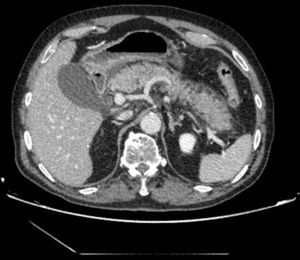

The patient is a 75-year-old male who presented with abdominal pain in the epigastrium that had been progressing for 12h, associated with elevated amylase and lipase levels, with no clinical–analytical signs of severity. The computed tomography scan revealed edema of the pancreas, with no necrosis (Fig. 1). The patient was hospitalized and treated with conservative treatment. Twenty-four hours later, the patient presented with multiple organ failure associated with generalized signs of peritonism; the patient was transferred to the ICU. A triple-contrast CT scan was repeated 30h after the initial scan, which demonstrated diffuse emphysematous pancreatitis, but no signs of perforation (Fig. 2). We decided to perform emergency surgery, which confirmed the findings, and cholecystectomy was carried out in conjunction with pancreatic drainage, transcystic cholangiography (normal) and laparostomy. After a torpid postoperative course, the patient died 48h after hospitalization.